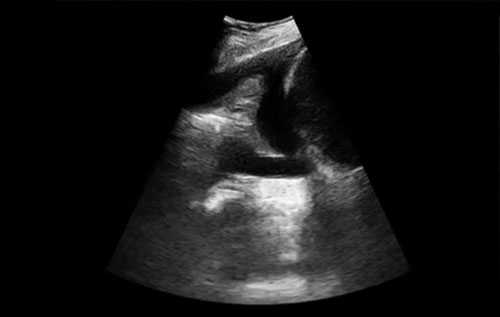

Paciente 63 anos, apresentando história de dispneia arrastada por várias semanas.